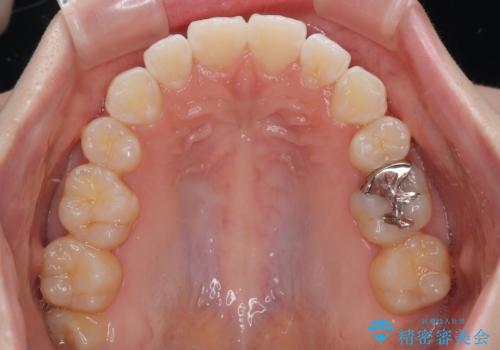

- くちばしのように飛び出した前歯を気にして来院された患者様です。

上下左右の第一小臼歯4本を抜歯して、ワイヤー装置にて矯正治療を行うこととしました。

舌の突出癖により、口元が突出しているだけでなく、上下前歯が非接触となっておりました。

舌のトレーニングをしっかりと行っていただくことで、2年を切って治療を終えるとともに

、上下前歯を接触させることができました。